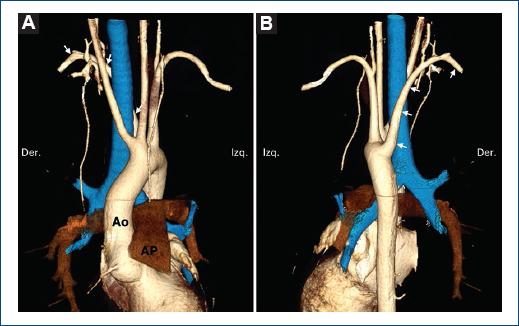

La arteria subclavia aberrante (Figs. 1 y 2), presente en el 82.6%, se analizó frente a otras variables de la siguiente forma: el 52% de los casos se presentaron sin conducto arterioso, mientras que el 30.6% de los casos sí lo presentaban. El subtipo más frecuente fue el arco aórtico izquierdo con subclavia derecha aberrante sin conducto arterioso, en el 36%, seguido por el arco aórtico izquierdo con subclavia derecha aberrante y conducto arterioso, en el 22.5% de los casos de anillos vasculares.

Figura 1 Subclavia derecha aberrante. Reconstrucciones volumétricas a partir de tomografía cardiaca en vista anterior (A) y posterior (B). Paciente de 8 años en abordaje por síndrome de Marfan. La aorta tiene diámetros normales, pero se documentó arteria subclavia derecha aberrante (flechas); además, ambas carótidas comunes tienen un origen compartido. En azul se representa la vía aérea. Ao: aorta; AP: arteria pulmonar.

Figura 2 Subclavia izquierda aberrante. Reconstrucciones volumétricas a partir de tomografía cardiaca en vista anterior (A) y posterior (B). Paciente de 5 meses que debuta con cianosis. Se concluyó portador de tetralogía de Fallot con arco aórtico derecho y subclavia izquierda aberrante (flechas). En azul se representa la vía aérea. Ao: aorta; AP: arteria pulmonar.